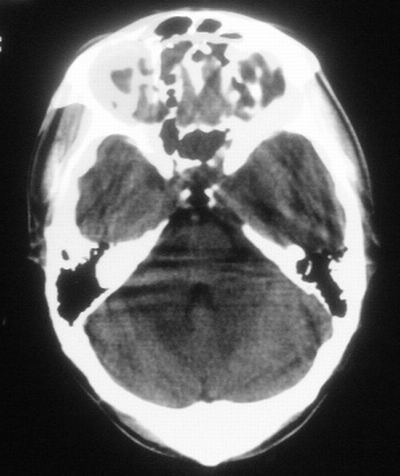

患者,男,30岁,右侧面部麻木,右上肢活动受限27小时。pe:神清、呼吸平稳,口角左歪,右上肢活动受限,右手掌握力消失,右侧躯体痛觉减退。

第一次颅脑ct扫描:左侧额顶叶血肿。